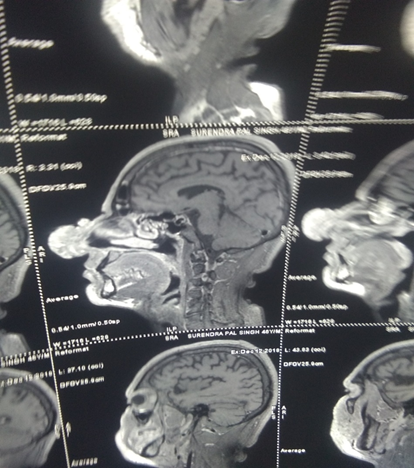

A 45 years old patient came to our OPD with a giant swelling of nose which was causing upper airways obstruction and difficulty in eating and breathing. It caused a lot of aesthetic and psycho-social disturbance to the patient (Figure 1). MRI of the patient showeda large well defined extensive cutaneous lobulated tumor with complete obstruction of the columella (Figure 2). No area of diffusion restriction and post contrast enhancement of soft tissues was noted.Surgical excision of the nasal swelling and full-thickness skin grafting of the defect was done.1

Figure 2 MRI scan reveals extensive cutaneous lobulated tumor with complete obstruction of the both nostrils.